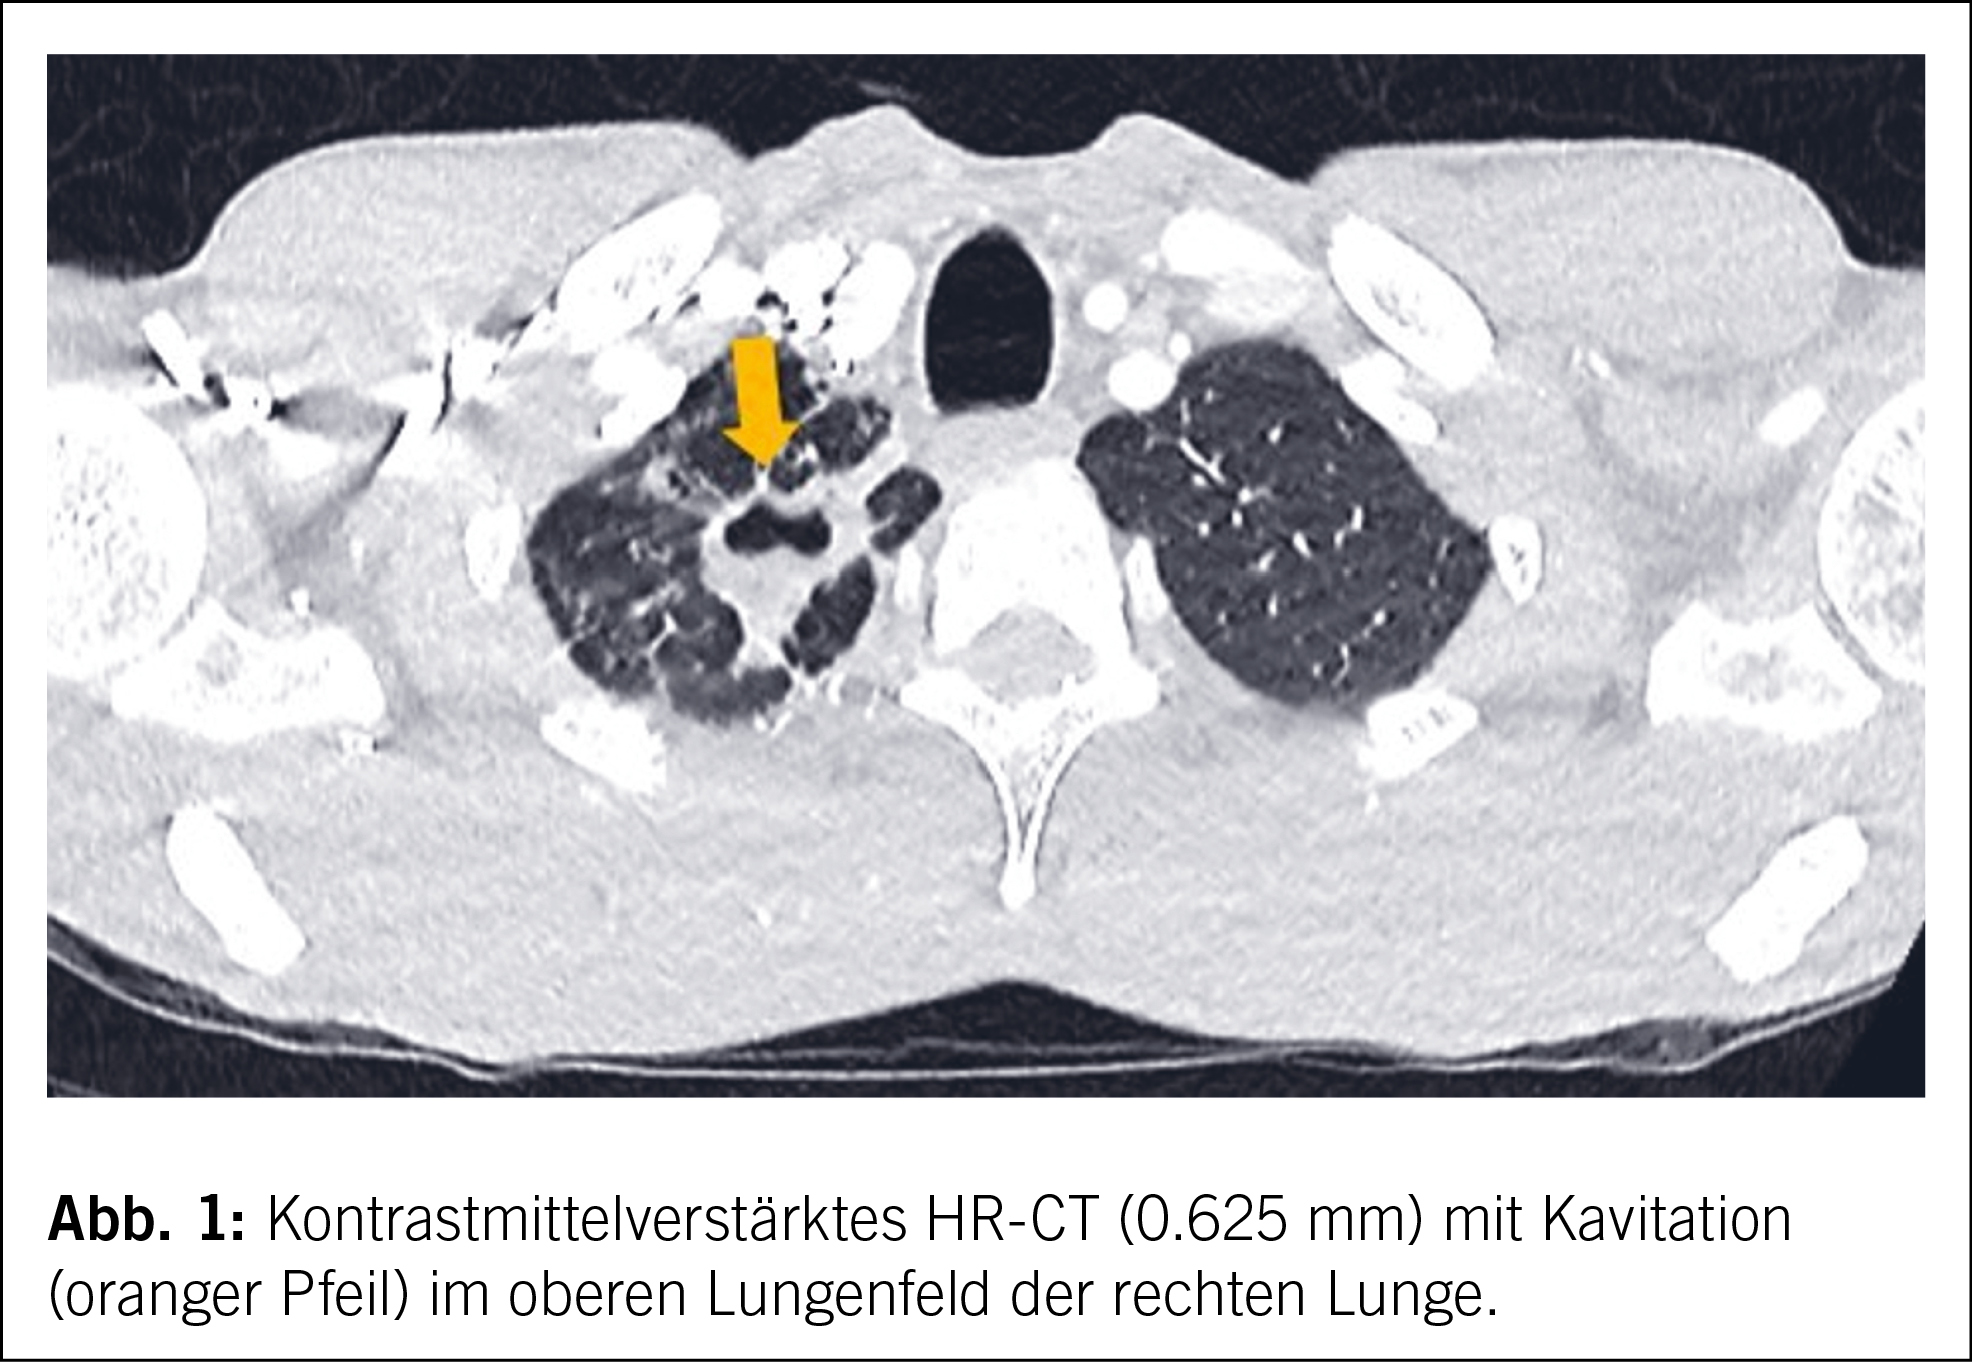

- XDR-Tuberkulose: Nicht nur medizinisch eine Herausforderung